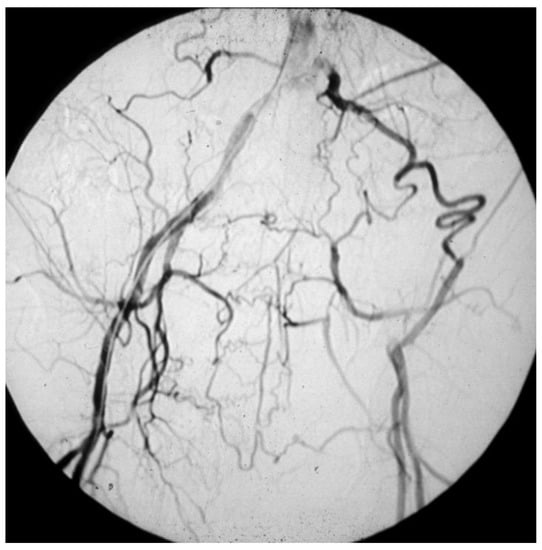

Those who have a masked LEAD, since they do not present IC: reasons range from the development of efficient arterial collateral circulation (Figure 8) to limited mobility, up to being bedridden [51];

Figure 8. Arteriography showing obstruction of the left iliac axis, with an efficient collateral pathway revascularizing the common femoral artery. Depending on his/her age and lifestyle, this patient can eventually be asymptomatic or paucisymptomatic for intermittent claudication. An accurate physical examination (detecting the absence of the left femoral pulse), and the subsequent left ankle-brachial index (founded to be reduced) can easily allow for this patient to be classified as vasculopathic.